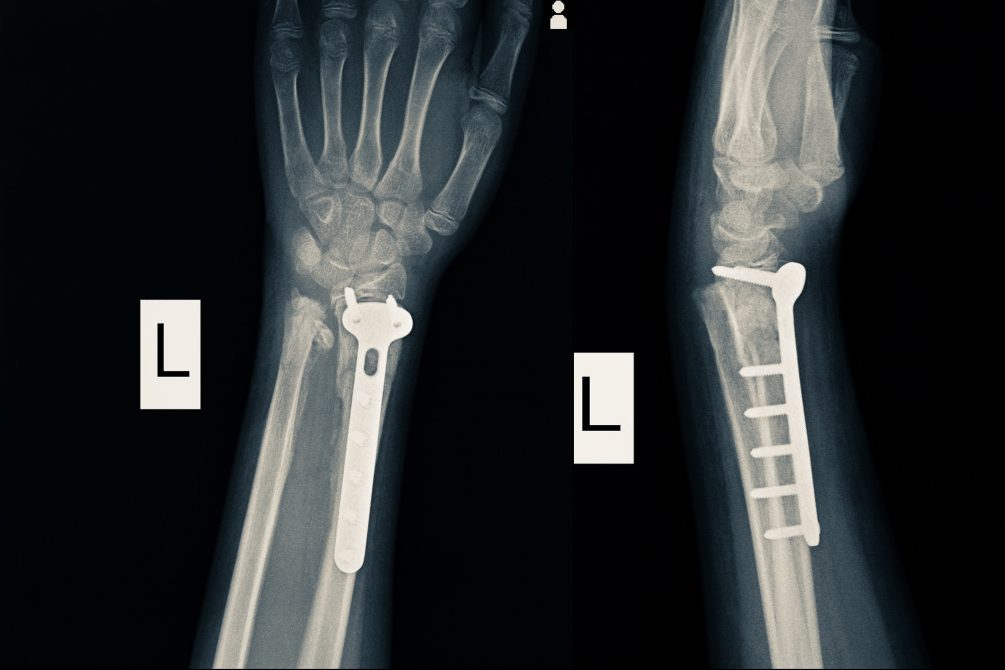

Hand Therapy For Broken Wrist at Norman Baily blog Wrist Pain Restricted Movement injury or inflammation of the tendon can cause the sheath to thicken, enlarging it and restricting the fluidity of movement. Even though the wrist is a small part of the body, it’s comprised of eight bones, as well as. Your symptoms might also give you an idea of what's causing. a detailed history alone may lead to a. Wrist Pain Restricted Movement.

A Broken Wrist What to Expect From the Recovery Process Maryland Wrist Pain Restricted Movement 1 the physician must characterize the precise nature of the. Your symptoms might also give you an idea of what's causing. carpal tunnel syndrome. injury or inflammation of the tendon can cause the sheath to thicken, enlarging it and restricting the fluidity of movement. wrist tendinitis (tendonitis) is inflammation in the tendons that connect your lower arm. Wrist Pain Restricted Movement.